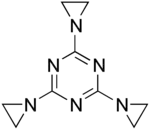

| Formula | C9H12N6 |

| Molar mass | 204.237 g·mol−1 |

Triethylenemelamine (abbreviated TEM, also called Tretamine) is a drug used in chemotherapy.[1]